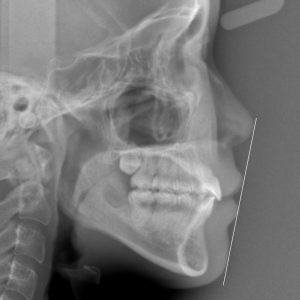

新着情報 1602 終了時 セファロ側面 – コピー Tweet 投稿日 : 2025年09月04日(木)カテゴリー : コメントを残す コメントをキャンセルメールアドレスが公開されることはありません。 * が付いている欄は必須項目ですコメント 名前 * メール * サイト 22歳 女性 「 出っ歯、口もとを 治してほしい」治療期間22か月(上下顎前突症) ≫